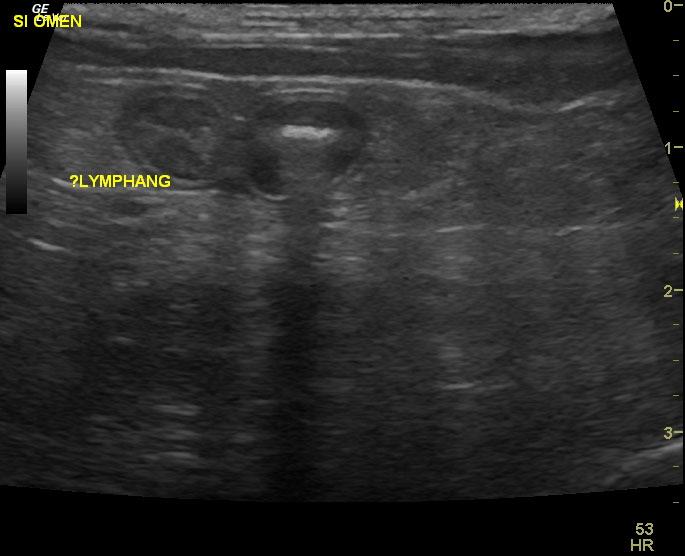

A 9 year old MN Maltese dog was presented for evaluation of progressive anorexia and soft feces. Physical examination and rectal palpation were both within normal limits. Fecal and urinalysis, CBC, serum biochemistry, cPl, and survey radiographs of the thorax and abdomen were all within normal limits.